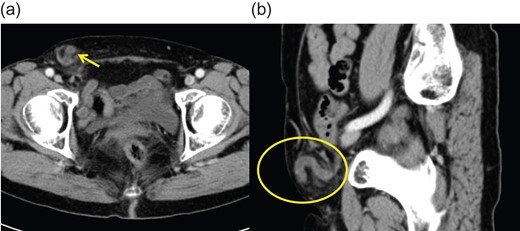

A 74-year-old woman with aplastic anaemia and hypertension who complained of a bulging mass and tenderness in the right inguinal area was referred to our department. She was afebrile, normotensive, and denied abdominal pain, bloating, nausea or vomiting. Upon physical examination, a swelling mass measuring 3 cm × 3 cm was observed just below the right inguinal ligament. The swelling was irreducible but not strangulated. Laboratory examination findings showed that the white blood cell count and C-reactive protein level of the patient were within the normal range, but the percentage of neutrophilic leucocytes was slightly increased, at 73.7%. Abdominal enhanced computed tomography (CT) revealed a swelling and an enhanced appendix within the femoral hernia (Fig. 1). Hence, a diagnosis of de Garengeot hernia with suspected acute appendicitis was made, and surgery was performed. A 12-mm trocar was inserted under the umbilicus, and a 30° laparoscope was used to examine the abdominal cavity. No ascites or dilated bowels were observed. The major part of the appendix passed through the femoral orifice (Fig. 2). Then, two additional 5-mm trocars were inserted in the left lower and middle abdominal regions. The hernia could be reduced by deliberately pulling the appendix. A necrotic and inflamed appendix was detected (Fig. 3a). Subsequently, laparoscopic appendectomy was performed. Hernioplasty was performed via the anterior approach to prevent properitoneal contamination. The hernial defect was repaired using a mesh plug. The incarcerated hernia sac was reduced via the extraperitoneum, and it was then ligated and resected via laparoscopy (Fig. 3b). The pathological findings showed acute purulent appendicitis. The postoperative course of the patient was uneventful, without any surgical site infection (SSI), and she was discharged on the postoperative Day 8.

Abdominal enhanced computed tomography imaging showing (a) the enhanced tubular structure in the femoral hernia and (b) the caecum.